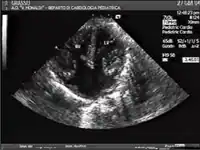

Ultrasound showing a complete atrioventricular septal defect

AVSDs can be detected by cardiac auscultation; they cause atypical murmurs and loud heart tones. Confirmation of findings from cardiac auscultation can be obtained with a cardiac ultrasound (echocardiography - less invasive) and cardiac catheterization (more invasive). It is also possible to diagnose AVSD in-utero via routine fetal ultrasounds or, more conclusively, fetal echocardiograms.[3]